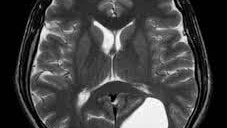

Магнитно-резонансная томография головного мозга – это современный метод обследования, который может дать важную информацию для диагностики опухолевых, воспалительных и демиелинизирующих заболеваний самого мозга и мозговых оболочек...

МРТ головного мозга – это хорошо апробированный и надежный метод диагностики, который основывается на свойствах магнитного поля и отличается повышенной информативностью и точностью. Суть метода заключается в том, что под воздействием радиомагнитных импульсов в органах человека возникают ответные волновые сигналы, которые с помощью компьютера томографа преобразовываются в изображения в нескольких плоскостях. Основной задачей магнитно-резонансной диагностики является постановка точного диагноза, а также контроль динамики после назначенного лечения или операционного вмешательства...